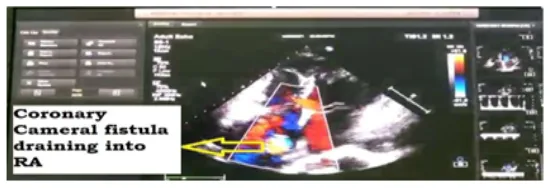

A 53-year-old female known case of hypertension presented with chest pain, palpitations, and progressive dyspnea on exertion for one year, ECG suggestive of Atrial Fibrillation, 2D Echo Findings (Fig1): suspicious RSOV shunt into RA, dilated RA, mild AR, normal systolic function. Coronary angiogram was suggestive of coronary Cameral Fistula from aneurysmal RCA to RA.

Operative finding: Coronary cameral fistula of 20mm size identified draining into RA at SVC junction (Fig3). Saphenous vein graft used for distal anastomosis to mid-RCA distal to aneurysmal segment. Following the aortic cross-clamp, an aortotomy has been performed. Left-side cardioplegia is given through left coronary ostia and right-side through vein graft for adequate myocardial protection. Aneurysmal dilated proximal RCA opened, and the ostium of mid-RCA was identified, closed with pledgeted suture excluded from the aneurysmal part; RCA is closed with a dacron patch and closed in double layer. The fistula opening in RA is closed with the pericardial patch (Fig 4). RA closed in layers. Weaned from cardiopulmonary bypass and decannulated.